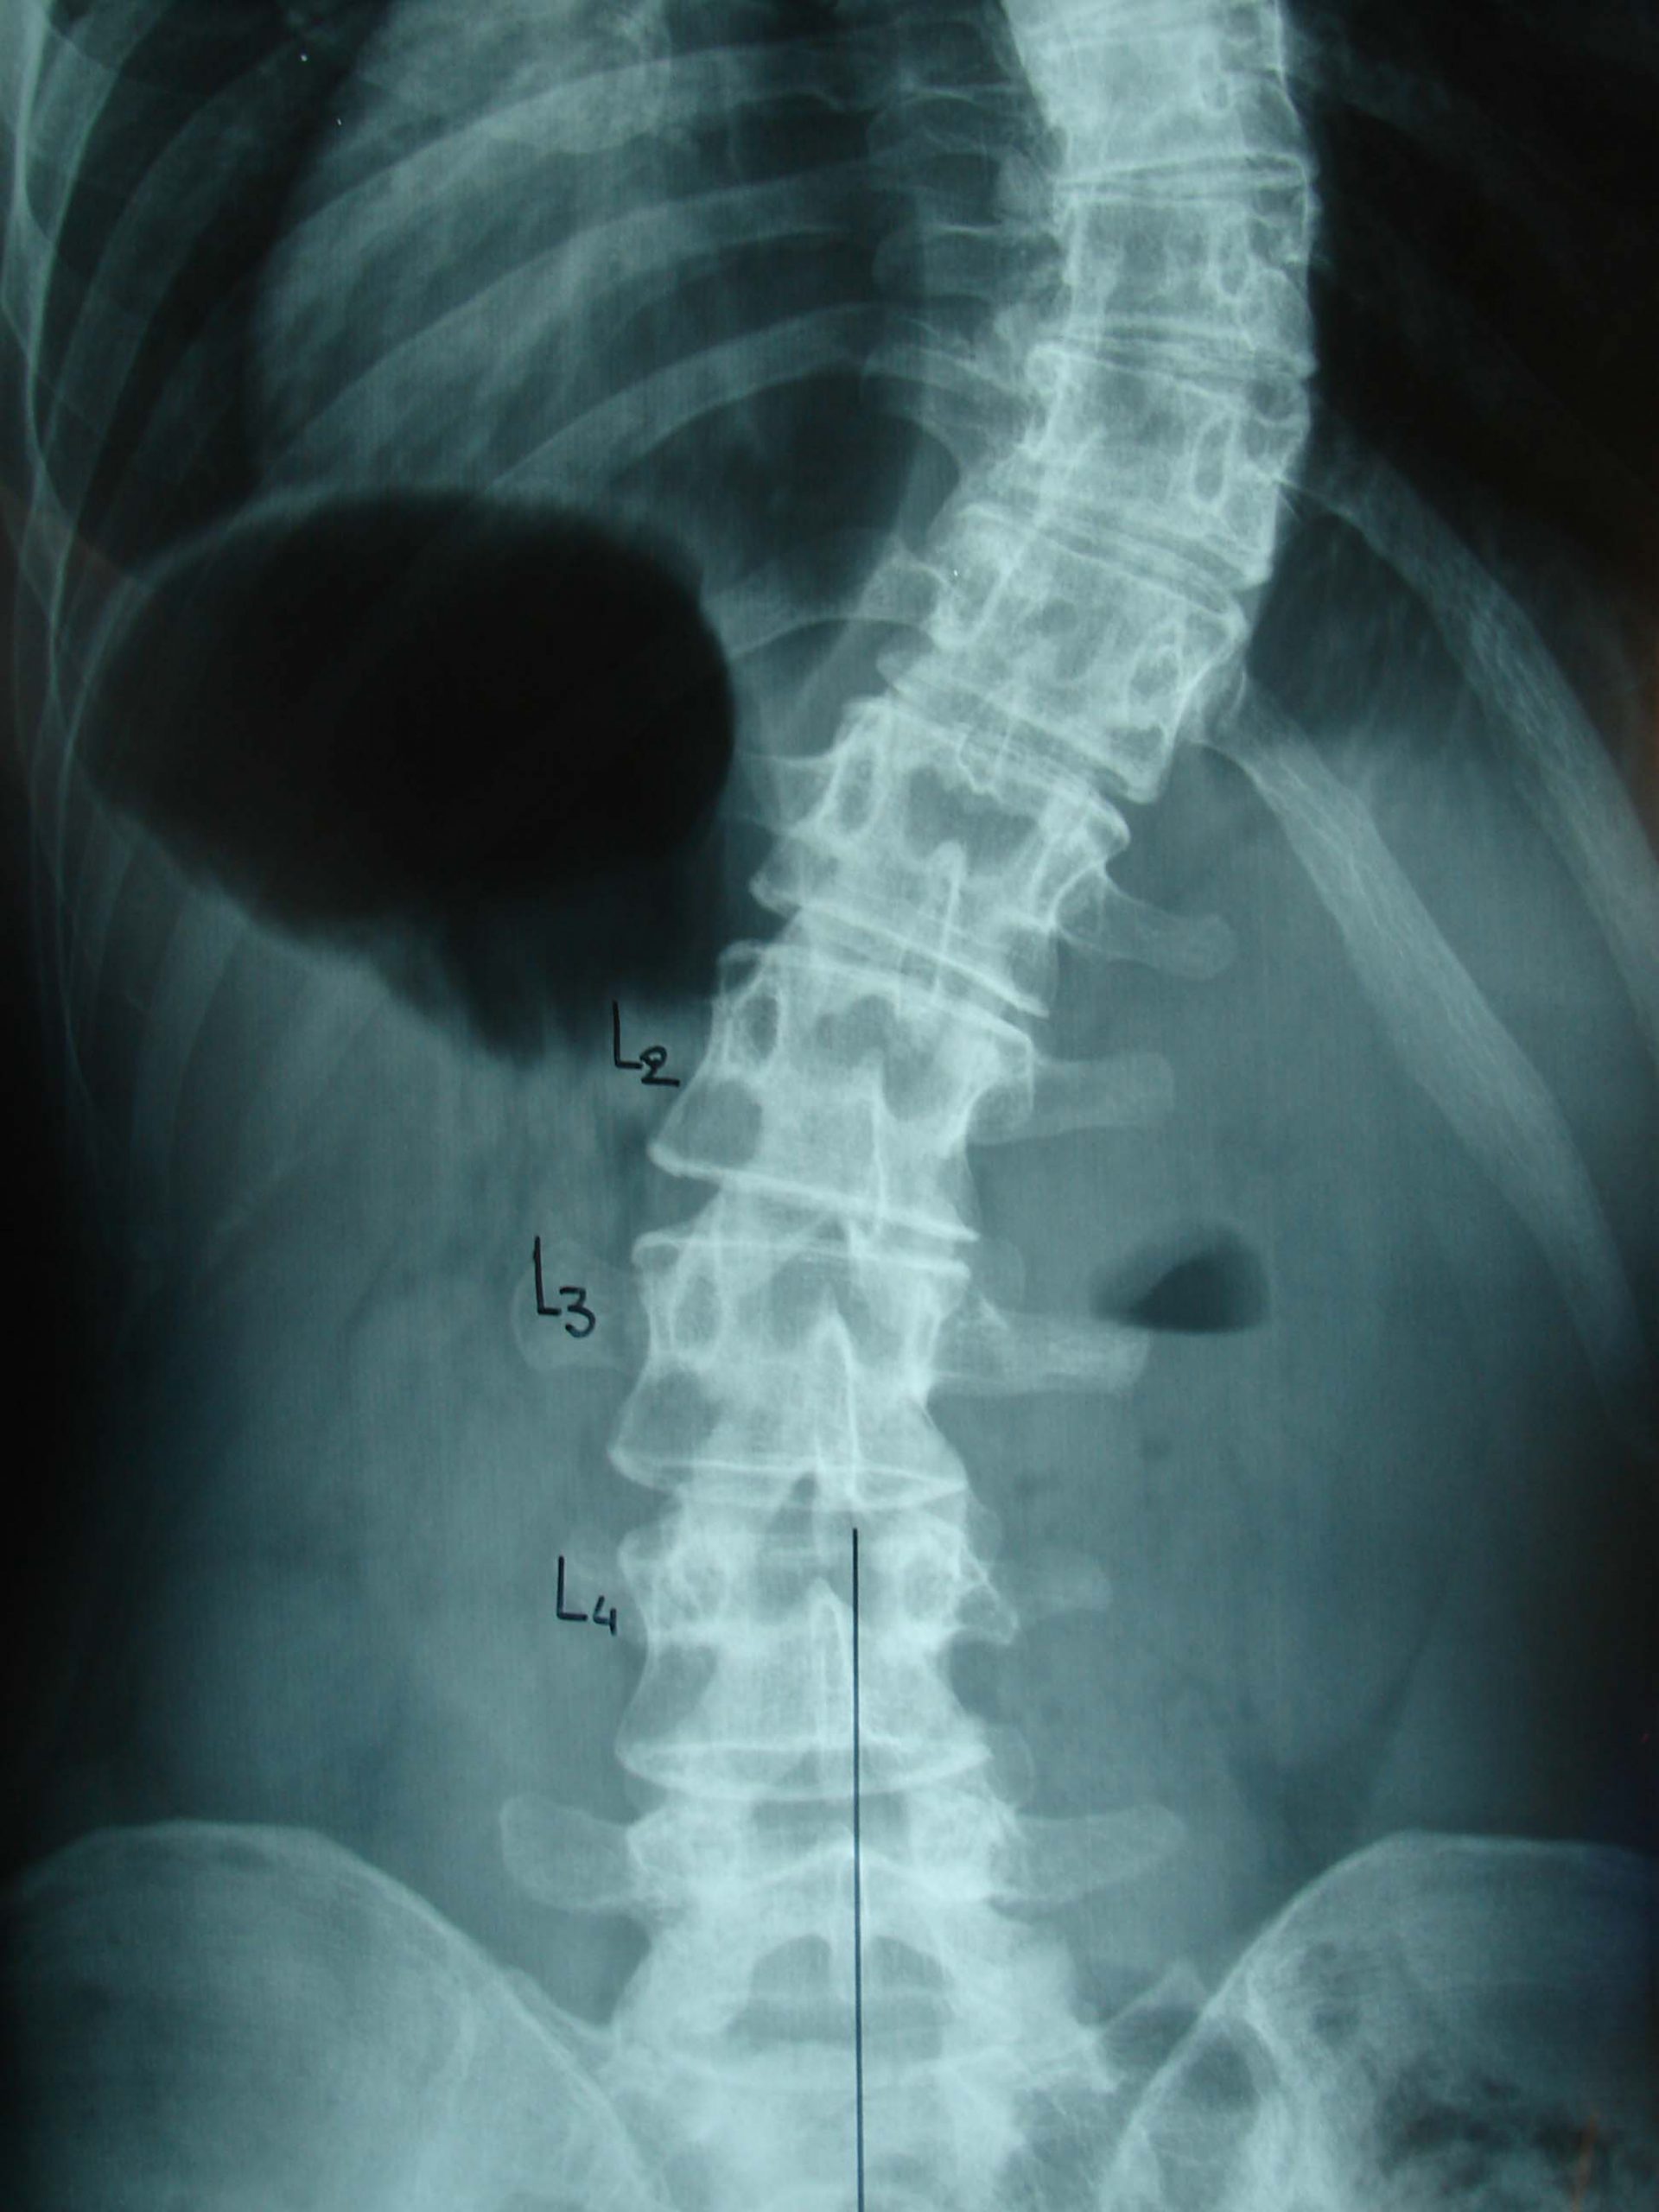

- α

- β

Εικόνα 3(α,β) α. Προσθιοπισθία ακτινογραφία Θωρακικής Μοίρας της Σπονδυλικής Στήλης (Θ.Μ.Σ.Σ) σε ηλικία 16 χρονών, φορώντας τον κηδεμόνα. Παρατηρείται ότι το θωρακικό κύρτωμα εντός του κηδεμόνα είναι 40ο. β. Ακτινογραφία σε ηλικία 18 χρονών, φορώντας τον κηδεμόνα. Το θωρακικό κύρτωμα έχει φθάσει στις 50ο μοίρες.